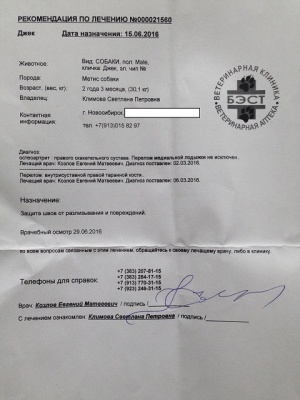

Лист приема и назначений от 15.06.2016, итоговый чек за период 02.03.2016 - 07.06.2016.

– оплата приема от 15.06.2016 и от 01.07.2016 хирург Козлов Евгений Матвеевич, клиника Бэст (чек 1, листы назначений – документ 1 и документ 2) – 650 руб.;

– оплата приема от 15.06.2016 и от 01.07.2016 хирург Козлов Евгений Матвеевич, клиника Бэст (чек 1, листы назначений – документ 1 и документ 2) – 650 руб.;

Последний раз были на приеме у Козлова Е.М. 01.07.2016.

Евгений Матвеевич не только произвел осмотр, но и внимательно посмотрел на Джека в движении, на улице, при ходьбе по лестнице. Следующий плановый осмотр через два месяца. Два месяца реабилитации и обучения жизни на четырех лапах.

Евгений Матвеевич не только произвел осмотр, но и внимательно посмотрел на Джека в движении, на улице, при ходьбе по лестнице. Следующий плановый осмотр через два месяца. Два месяца реабилитации и обучения жизни на четырех лапах.